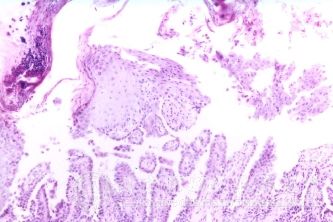

北京京城皮肤医院指出,自敏性皮炎的诊断:根据自敏性皮炎发病前先有原发性病损,经不适当处理或继发感染,随后随着原发灶病变恶化而四肢和躯干发生丘疱疹改变,自觉瘙痒,不难作出诊断。